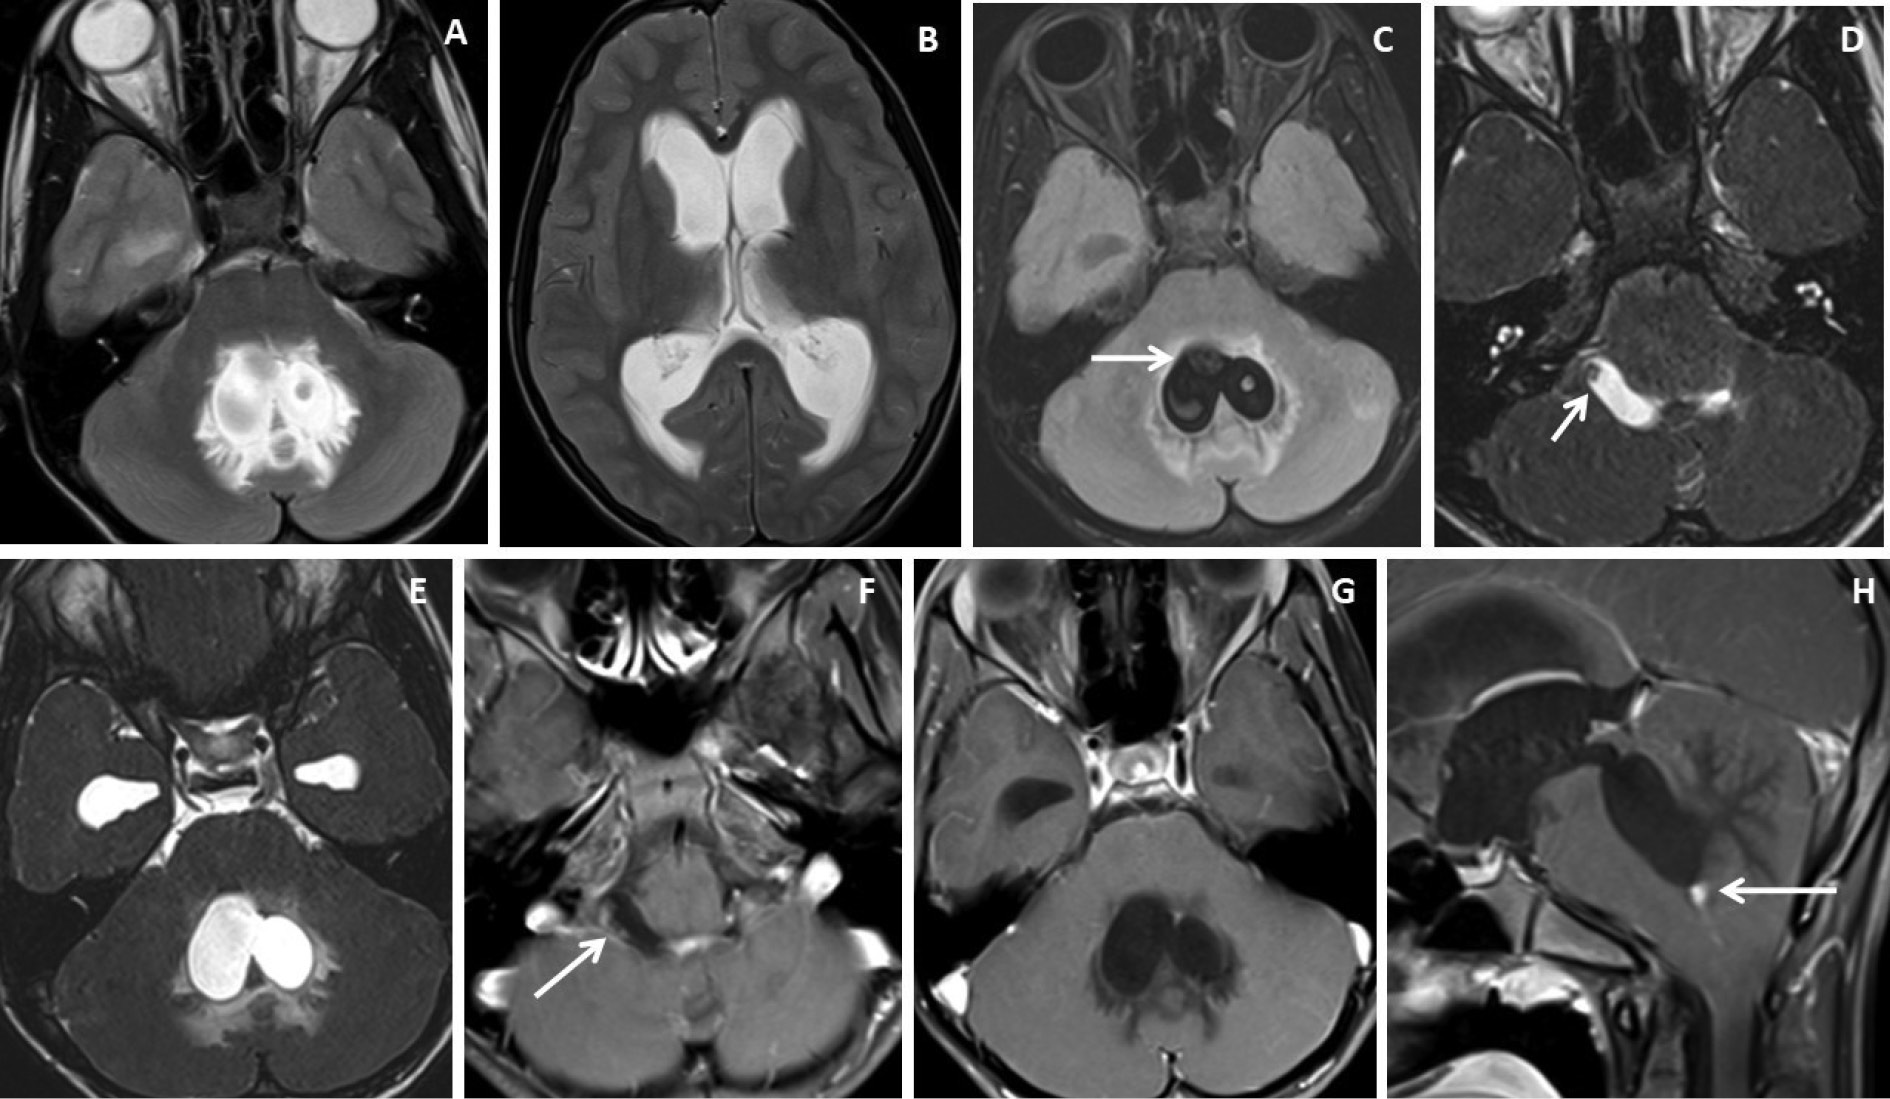

Figure 3. Brain magnetic resonance imaging of 25 years male with headache. (A-B) Axial T2WI and FLAIR images show distension and dilatation of the fourth ventricle with minimal periventricular CSF seepage. Variable signal intensity cystic lesions are seen within the fourth ventricle on the FLAIR image (arrow). (C-D) Axial and coronal heavily T2W images show multiple thin-walled hyperintense cystic lesions (arrows) with less hyperintense CSF signal within the 4th ventricle with variable sizes irregular nodules within. (E-F) Axial and sagittal T1W post-contrast image shows thin smooth enhancement of the intraventricular cyst (arrow) with enhancing irregular nodules. Post-contrast enhancement is also seen along the ependymal lining of the 4th ventricle, in posterior and inferior aspects.

Figure 4. Brain magnetic resonance imaging of 13 years male with severe headache, vomiting and acute neurological deterioration. (A-B) Axial T2WI images show marked distension and dilatation of the fourth ventricle with marked periventricular CSF seepage and supratentorial hydrocephalus. (C) Axial FLAIR image shows cystic lesions within the fourth ventricle (arrow). (D-E) Axial heavily T2W images show thin-walled hyperintense cystic lesions within the 4th ventricle with an oval to elongated appearing cystic lesion with scolex in the right foramen of Luschka (arrow). (F-H) Axial and sagittal T1W post-contrast image shows a thin peripheral enhancing cystic lesion with an irregular mural nodule in the right foramen of Luschka (arrow) and thin smooth enhancement of the intraventricular cysts. Nodular enhancement was seen in midline inferior margin of 4th ventricle near to foramen of Magendie (arrow).